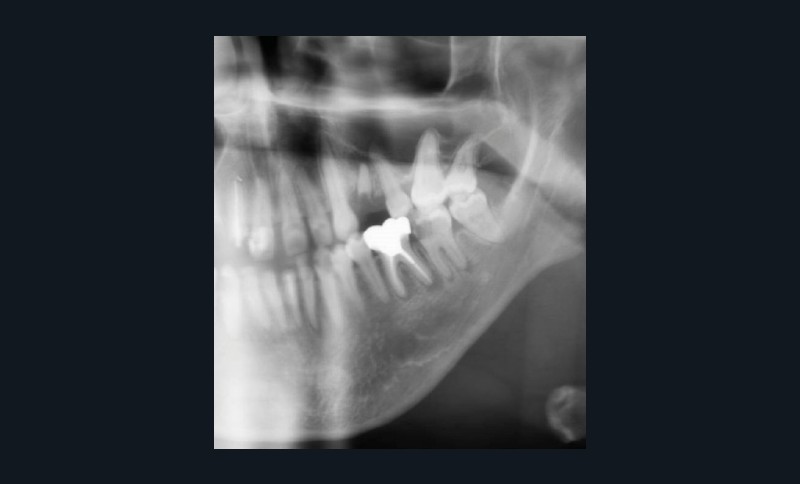

Le principal risque d’ostéonécrose en lien avec une biothérapie est dû à l’inhibiteur du RANKL, le dénosumab (commercialisé sous le nom de Xgeva® en indication oncologique, Prolia® en indication rhumatologique) (fig. 1). Cet anticorps bloque la liaison du RANKL à son récepteur, qui permet notamment l’activation des ostéoclastes. La résorption osseuse est alors bloquée, action intéressante dans le cadre d’une ostéoporose ou de métastases osseuses. Cependant, même si le mécanisme d’action est totalement différent, on retrouve les mêmes effets indésirables que ceux observés avec les bisphosphonates au niveau de la cavité orale. Les patients traités par anti-RANKL présenteront un risque d’ostéonécrose des mâchoires. Ce risque sera évidemment plus ou moins important en fonction de facteurs à rechercher : indication du traitement (oncologique ou rhumatologique), durée totale du traitement, date de dernière administration, corticothérapie associée, diabète, présence de foyers infectieux bucco-dentaires…

Pour les actes invasifs, une suspension de traitement pourra être discutée avec le médecin prescripteur, afin de réduire le risque infectieux au moment de l’acte, mais aussi en postopératoire [1, 2]. La thérapeutique sera reprise lorsque la cicatrisation sera complète. Il est évident que cette suspension de traitement ne doit pas altérer le pronostic de la pathologie et l’état général du patient. En cas d’urgence, les actes nécessaires doivent être entrepris sans délai (fig. 3).

Les actes invasifs seront généralement précédés d’une antibioprophylaxie, qui pourra être prolongée en fonction de deux éléments : la nature de l’acte et le risque infectieux propre au patient [3].